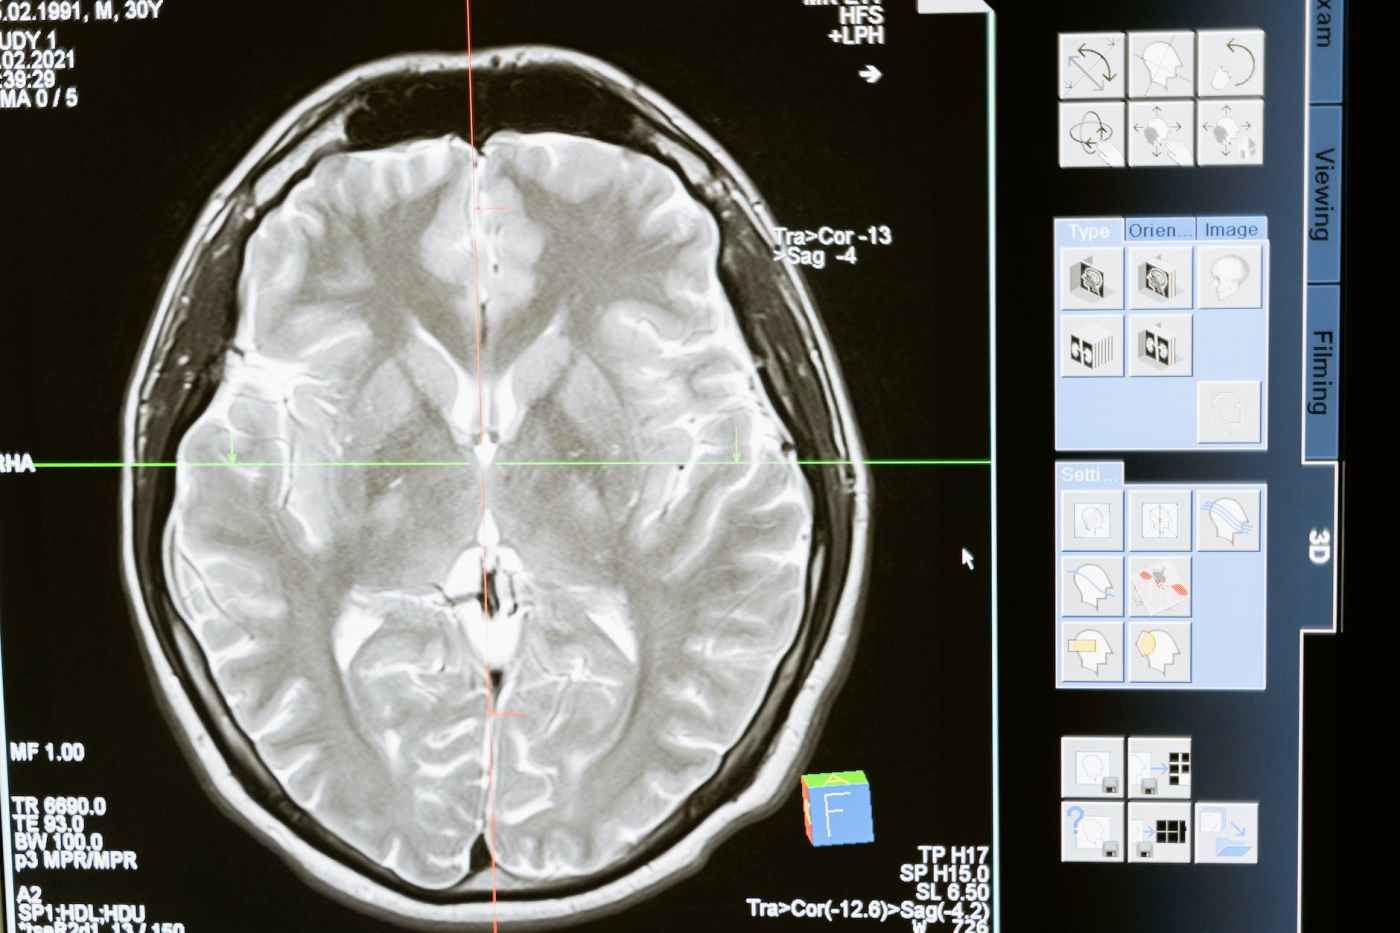

Neuroplasticity, the brain’s remarkable ability to change and adapt, has captivated the minds of researchers and scientists for decades. This phenomenon refers to the brain’s capacity to reorganize itself by forming new neural connections in response to learning, experience, and even injury. In this blog post, we will delve into the fascinating world of neuroplasticity and explore its implications for human development and rehabilitation.

At its core, neuroplasticity challenges the long-held belief that the brain is a fixed and unchanging organ. Instead, it highlights the brain’s inherent malleability, allowing it to continuously refine and rewire its neural pathways. This adaptability is not limited to specific regions of the brain but extends across its entirety, opening up a world of possibilities for growth and transformation.

Moreover, neuroplasticity plays a vital role in rehabilitation following brain injuries. In the past, it was believed that once the brain was damaged, recovery was highly unlikely. However, research has shown that the brain has an astonishing capacity to reorganize itself to some extent, even after significant injury. Through intensive therapy and targeted exercises, individuals can rewire their brain, allowing undamaged regions to assume the functions of the damaged ones. This process highlights the potential for recovery and offers hope to those affected by traumatic brain injuries or strokes.